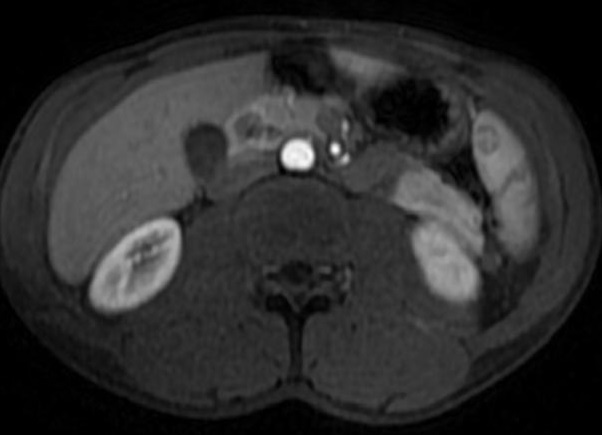

Image radiologique cholangio-wirsungo-IRM normal des

voies biliaires principale |